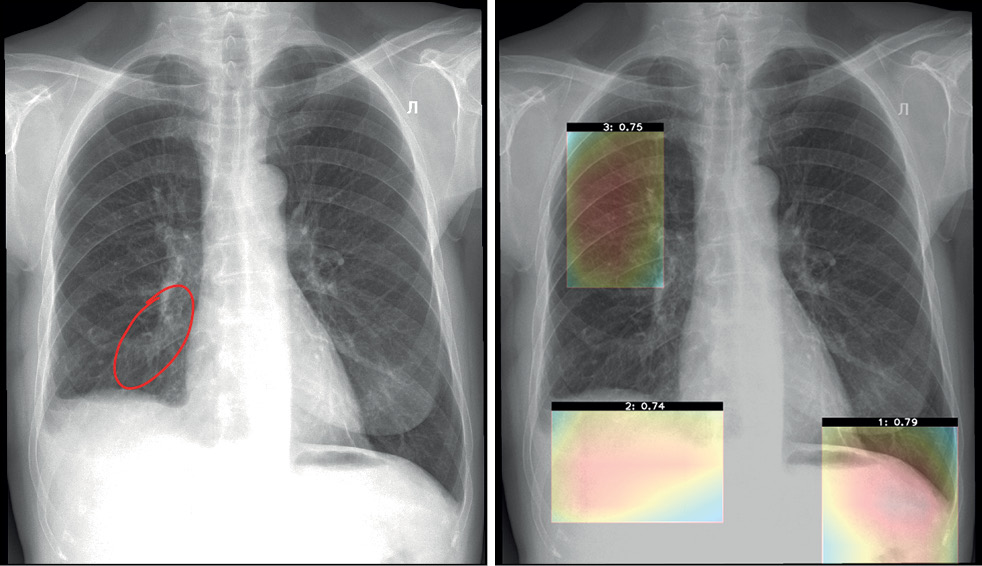

Functional testing is a stage wherein software functions specified by a supplier are checked for availability and functionality. This testing is performed at the technical and clinical levels. On a technical level, the software is assessed based on the following criteria: prioritization of research (triage), availability of an additional series of images from the software, presence of the other series’ name, presence of a graphical designation of software on the images of the different series, presence of a warning label “For research purposes only” on images and in DICOM SR, possibility of series synchronization, displaying the probability of abnormality, indication of the category of abnormality, and availability of complete DICOM SR protocol structure (Figures 2 and 3).

Fig. 2. Main components of the result of using artificial intelligence–based software with images: A reference example.

Fig. 3. Main components of the result of using artificial intelligence–based software with DICOM SR: A reference example.